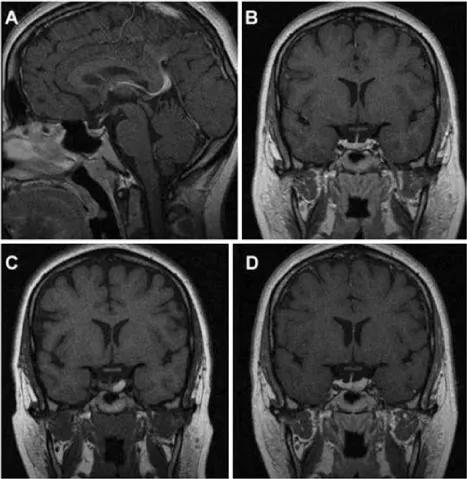

圖1,一名27歲女性患者的磁共振成像(MRI)資料,該患者因垂體微腺瘤接受William T.Couldwell教授的隨訪監(jiān)測,后續(xù)發(fā)生垂體卒中。

A、B:初次就診時獲得的矢狀位與冠狀位T1加權(quán)增強MRI,顯示垂體左側(cè)部一小腺瘤。

C、D:隨后復(fù)查的冠狀位T1加權(quán)平掃及增強MRI,可見原腫瘤區(qū)域出現(xiàn)出血信號,提示腺瘤內(nèi)卒中。